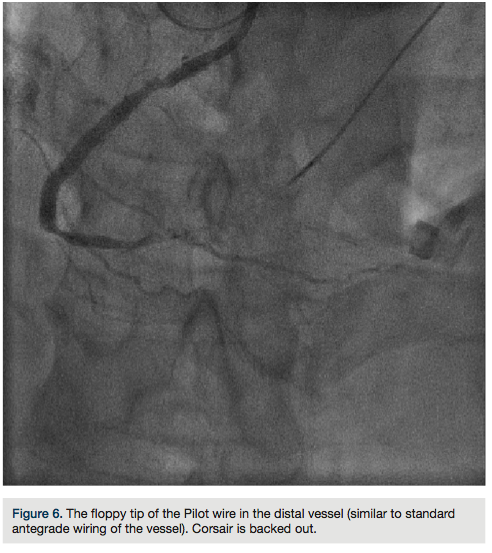

RCA (Figure 5). Using a Pilot wire (Abbott Vascular), we were able to advance in a retrograde fashion into the RCA guide, but the Corsair catheter was not long enough to go all the way (a 135 cm catheter was inadvertently opened instead of the 150 cm). Therefore, we trapped the Pilot wire into the RCA guide with a 2.5 x 20 Emerge balloon after removing the antegrade wire (the Pilot wire is hydrophilic; therefore, one needs to exercise caution when trapping). We removed the 135 cm Corsair and advanced a 150 cm Corsair retrograde into the RCA guide. We then removed the Pilot wire through the Corsair, running retrograde from the left guide to the right guide. We rewired the Corsair in an antegrade fashion, rather than

externalizing it in the left radial, through the RCA guide (this does sacrifice the ultimate rail for delivery of balloons or stents by eliminating the externalized wire). The floppy tip of the Pilot wire was now in the distal vessel (similar to standard antegrade wiring of the vessel) and we backed out the Corsair (Figure 6). We advanced a 2.5 x 30 mm balloon and predilated. Intravascular ultrasound (IVUS) (Boston Scientific) demonstrated the RCA was a fairly large vessel and therefore, a 4.0 x 38mm Promus drug-eluting stent was placed in the mid RCA. The distal lesion was treated. We dilated with a 3.0 x 30 mm balloon and noticed a distal dissection.